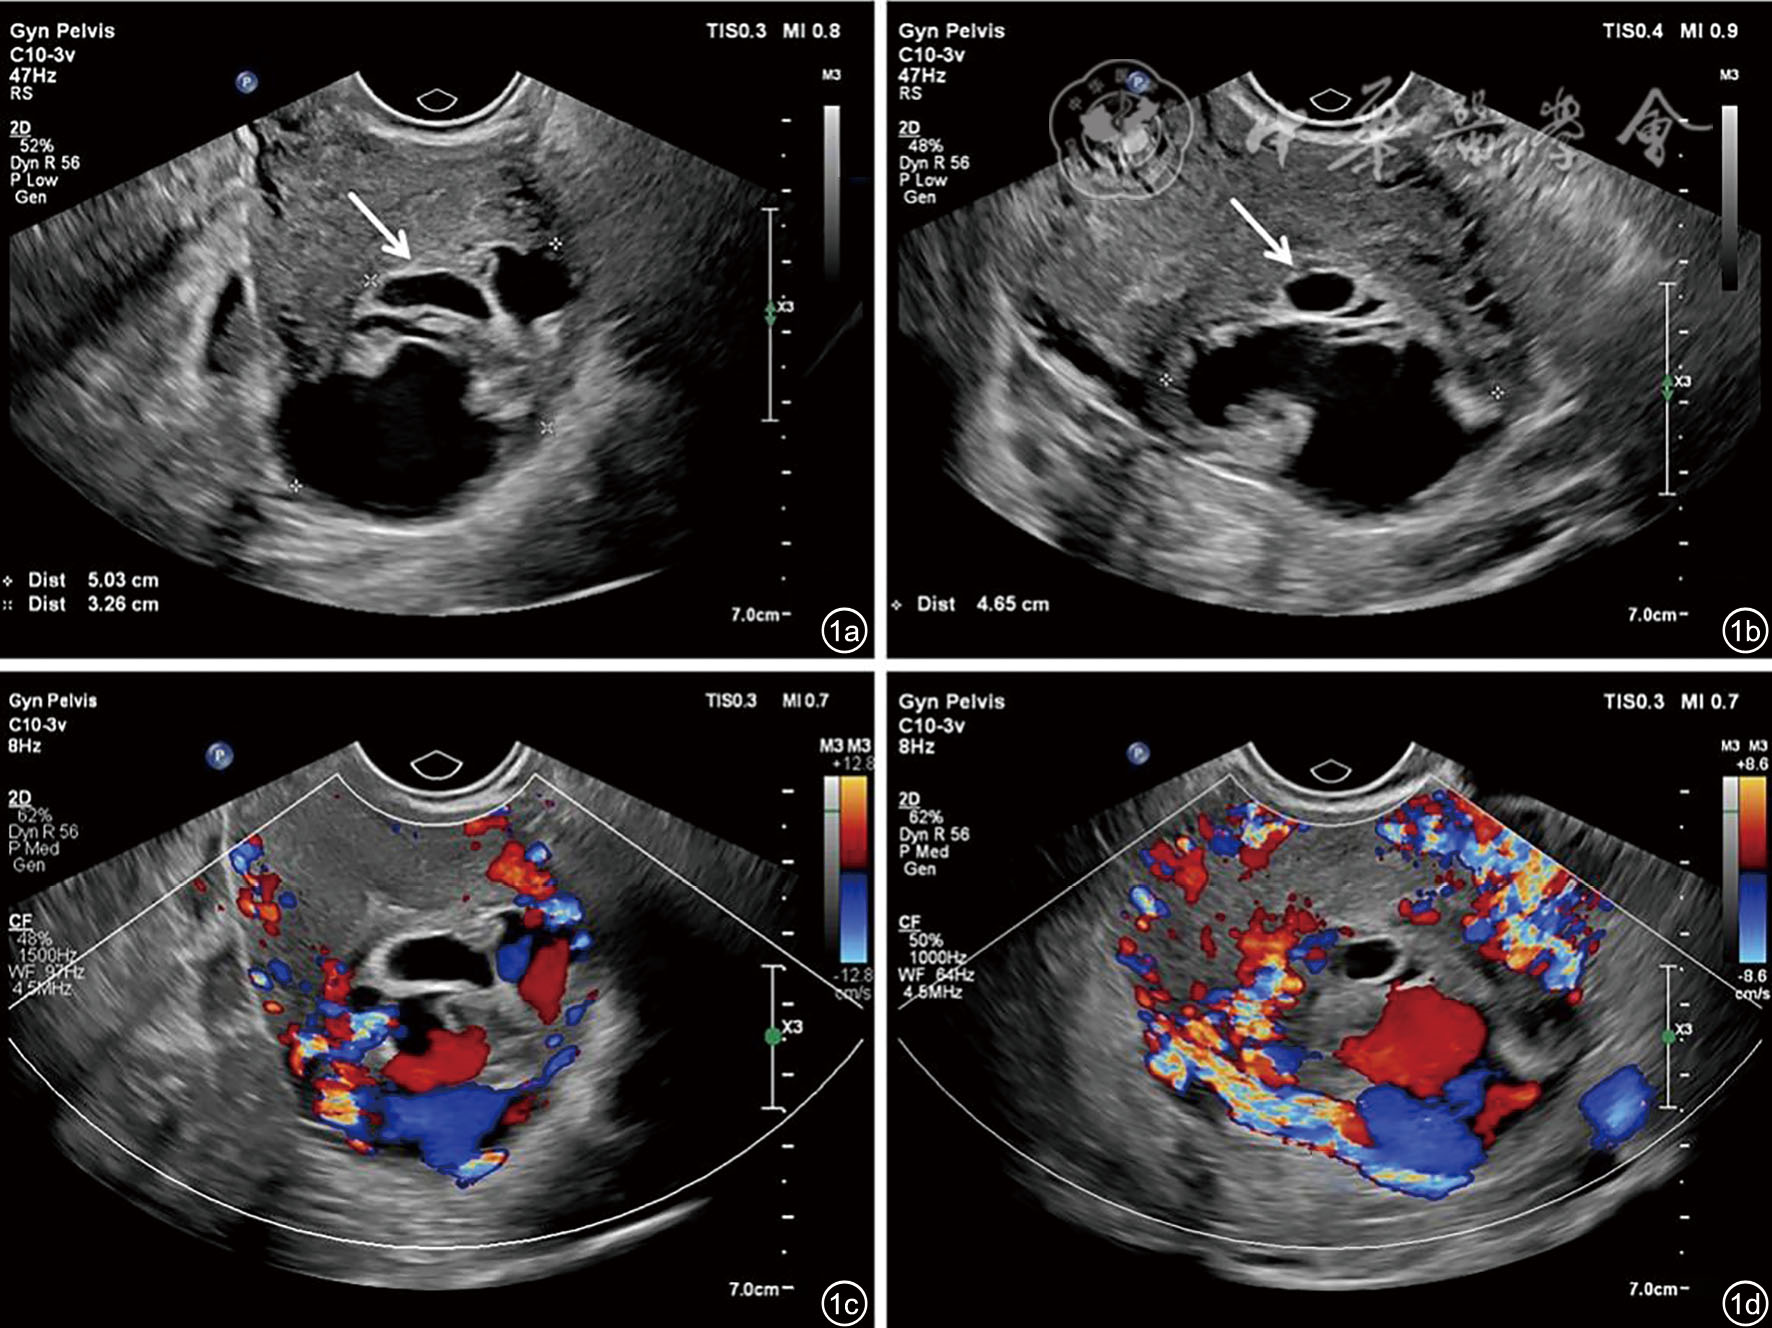

图3 肌壁间异位葡萄胎妊娠术中及病理图像。图a示腹腔镜术中见左侧宫底膨大、外突(箭头);图b病理图像示宫底肌层组织中见绒毛水肿(HE ×40);图c病理图像示滋养细胞增生(HE ×100)